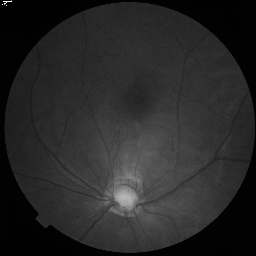

3.1.2 Synthetic Unlabeled Data Generation

To augment the limited real labeled data, high-fidelity synthetic images are generated using StyleGAN2-ADA [16]. The model’s Adaptive Discriminator Augmentation (ADA) mechanism dynamically adjusts augmentation probability to prevent discriminator overfitting on limited training samples, enabling realistic and diverse image generation even from minimal input. Figure 3 presents random selected synthetic images for the ACDC and FIVES datasets at the 5% and 10% labeled data splits.

We train StyleGAN2-ADA on the aforementioned 5% or 10% real labeled data. The quantity of generated synthetic images matches the remaining proportion of the full dataset (e.g., 90% or 95%), effectively serving as the unlabeled data input for the SRA-Seg framework.

FIVES dataset [14] consists of 800 high-quality multi-disease fundus images and annotated segmentation masks. We partition this dataset into 70% for training (560 images), 10% for validation, and 20% for testing. Similar to ACDC, we use 5% (28 images) and 10% (56 images) of the 560 training images as labeled data to simulate low-data availability, treating the remaining data as unlabeled.

Synthetic Data: For our experiments, high-fidelity synthetic images are generated using StyleGAN2-ADA [16] as described in Section 3.1.2. The model is trained exclusively on the limited percentage of real labeled data available for each dataset (e.g., 5% or 10%). For instance, when using 10% labeled data (136 images for ACDC or 56 for FIVES), StyleGAN2-ADA is trained solely on these specific images. Figure 3 shows random synthetic samples generated for both ACDC and FIVES datasets at 5% and 10% labeled data splits.